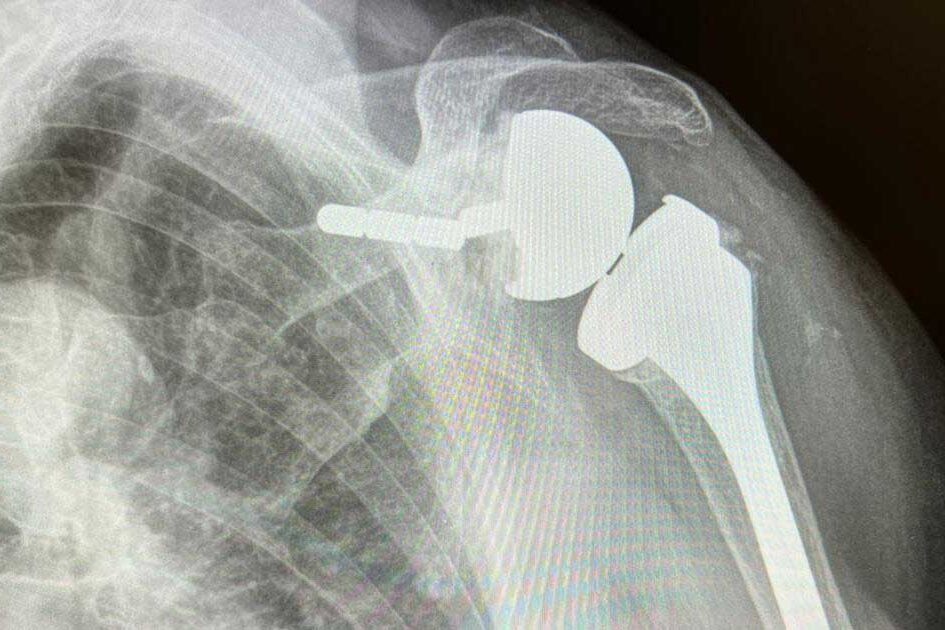

Febbre post intervento di protesi

Febbre dopo intervento di protesi: un fenomeno comune La febbre dopo operazione di protesi di spalla (febbre post intervento) è una preoccupazione comune tra i pazienti. Spesso, entro una settimana dall’operazione, i pazienti possono sperimentare una temperatura corporea di 37°, 38° o anche 38,5°. Tuttavia, queste temperature sono considerate accettabili nel periodo post-operatorio. Questo perché…